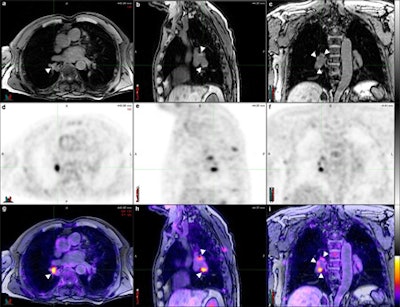

Axial (a), sagittal (b), and coronal (c) T1 fat-saturated MR images reconstructed from a volumetric 3D T1-weighted gradient-echo dataset, corresponding PET (d, e, f) and PET/MR fusion images (g, h, i). Pathologically increased tracer uptake discloses the neoplastic nature of the visualized lymph nodes. There is excellent soft-tissue contrast in MRI, which allows for the clear delineation of lymph nodes (arrowheads) and their distinction from vascular structures despite the absence of intravenous contrast.All 11 patients completed both examinations, and no adverse events were reported. Four experienced readers reviewed the results to determine the N stage of the patients with each hybrid imaging method in a randomized blinded way.